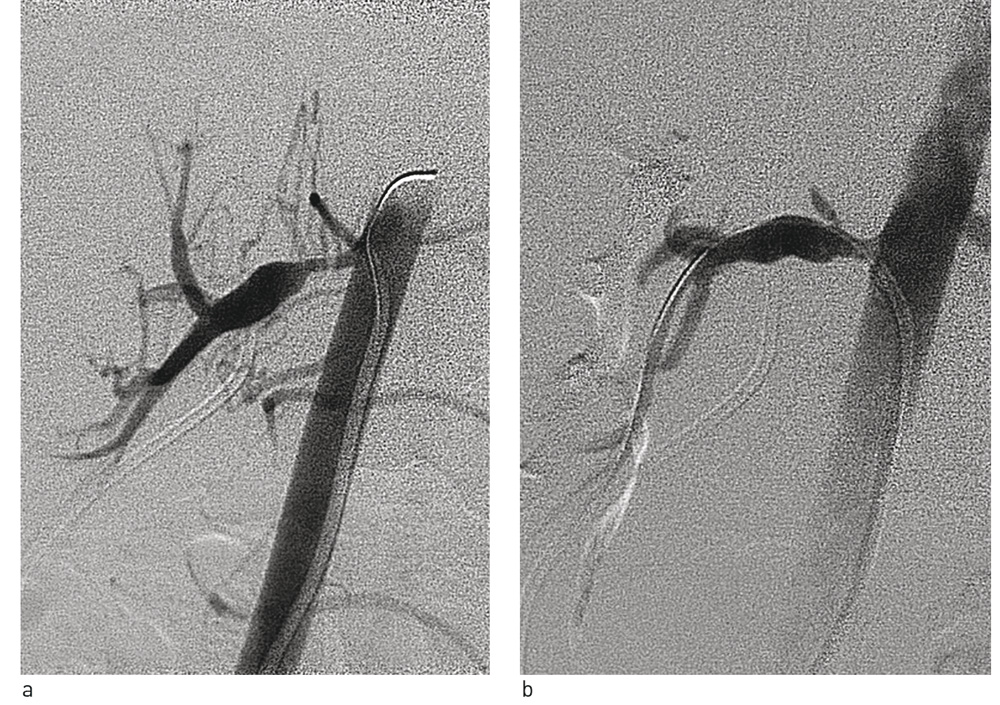

Alle de invasive prosedyrene ble utført i generell narkose. Ved perkutan transluminal renal angioplastikk ble nyrearterier kateterisert med føringskatetre og 0,014’ ledesonde. Etter diagnostisk angiografi ble det utført ballongdilatasjon med koronarballonger med diameter 2 – 4 mm. I tre tilfeller ble skjærende ballonger (cutting balloon) med diameter 3,5 – 5 mm brukt.

Pasientene ble behandlet med følgende invasive metoder: fem pasienter fikk utført perkutan transluminal renal angioplastikk (fig 1), hos én pasient ble en vaskulær malformasjon i nyren lukket med coil, syv pasienter fikk kirurgisk behandling (seks nefrektomi og én autotransplantasjon) og to pasienter fikk både perkutan transluminal renal angioplastikk og kirurgisk behandling. Hos ti av disse 15 pasientene ble blodtrykket gunstigere etter behandlingen. Resultater for en pasient manglet.